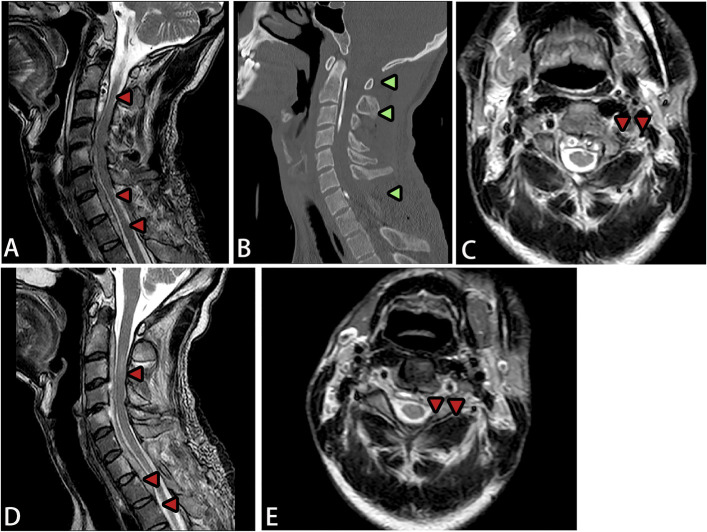

脊柱结核引起的脓肿通常发生在椎体的前部和外侧区域,常以冷脓肿的形式延伸至棘旁肌肉。虽然脊柱结核引起的椎管内脓肿很常见,但脊髓腹侧硬膜外腔纵向广泛脓肿的病例并没有很好的文献记载。该病的特点是发病隐匿,进展迅速,并具有不可逆转的神经损伤的高风险,突出了早期诊断和及时治疗的必要性。本文回顾了2例罕见的脊柱长节段结核性硬膜外脓肿,经过精确的手术干预和标准化的抗结核治疗,两例患者的症状均有显著改善。长节段结核性脊髓硬膜外脓肿(SEA)是一种非常罕见的并发症,可能导致严重的神经功能损害,磁共振成像显示广泛的脊髓硬膜外脓肿。临床表现,如颈部僵硬,容易被误认为结核性脑病;因此,建议使用增强MRI来鉴别SEA和结核性脑病。局部减压置管引流有助于保持神经功能,明确病因诊断,指导后续治疗。早期、充分和全面的抗结核治疗是成功管理的关键。

» Abscesses caused by spinal tuberculosis typically occur in the anterior and lateral regions of the vertebral bodies, often extending to the paraspinal muscles as cold abscesses. Although intraspinal abscesses due to spinal tuberculosis are very common, cases with longitudinally extensive abscesses in the ventral epidural space of the spinal cord are not well-documented. The disease is characterized by insidious onset, rapid progression, and a high risk of irreversible neurological damage, highlighting the necessity for early diagnosis and prompt treatment. » This review presents 2 rare cases of long-segment tuberculous spinal epidural abscesses, with both patients achieving significant symptom improvement after precise surgical intervention and standardized antituberculosis therapy. A long-segment tuberculous spinal epidural abscess (SEA) is an extremely rare complication that may cause severe neurological impairment, and magnetic resonance imaging revealed extensive spinal epidural abscesses. Clinical manifestations, such as neck stiffness, can easily be mistaken for tuberculous encephalopathy; therefore, contrast-enhanced MRI is recommended to differentiate a SEA from tuberculous encephalopathy. » Local decompression with catheter drainage can help preserve neurological function, establish a definitive etiological diagnosis, and guide subsequent treatment. Early, adequate, and comprehensive antituberculosis therapy is crucial for successful management.